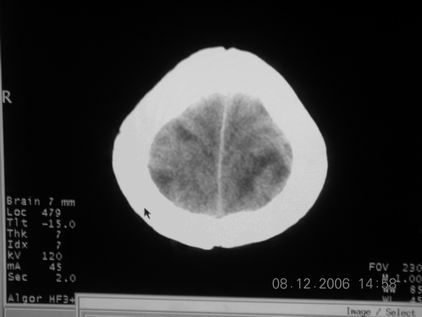

标题: CT11164:男,46岁,白血病患者,,大家看看. [打印本页]

标题: CT11164:男,46岁,白血病患者,,大家看看.

以前的片子,病史忘了,男,46岁,白血病患者,后来到中山二院诊断为

谁见过白血病中枢系统改变是怎么样的吗?

多发性脑脓肿?

白血病脑浸润。

1 多发脑脓肿可能性大.>2 白血病浸润.

白血病脑浸润。没见过!但结合病史应首先考虑此病。